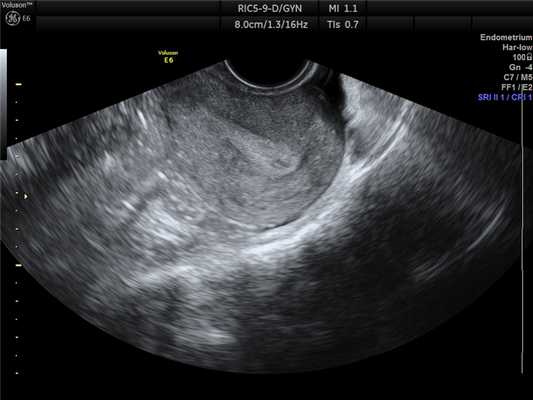

Номальные яичники

Рис. 2. Нормальный яичник с фолликулряным аппаратом.

Доминантного фолликула нет, поскольку исследование проводилось на 3 день менструального цикла.

При оценке состояния яичников по УЗИ определяется:

- Положение яичников.

В норме расположены по бокам от матки, чаще всего несимметрично, на небольшом расстоянии от углов матки. Форма яичников, как правило, овальная, при этом правый и левый яичники совершенно не идентичны друг другу. - Размеры яичников (продольный, передне-задний и поперечный).

Средние значения размеров нормальных яичников в длину от 2,4 до 4,0 см, переднее-заднего от 1,5 до 2,5 мм. - Структура яичников.

В норме яичники состоят из капсулы и фолликулов различной степени зрелости (в первой фазе цикла). Во второй фазе цикла, как правило, визуализируется желтое тело - признак произошедшей овуляции. Число фолликулов может быть неодинаковым слева и справа. Зреющий фолликул выявляется уже в первой фазе цикла и достигает к овуляции максимальных размеров, в среднем около 20 мм.

Содержимое доминантного фолликула однородное, поскольку он содержит фолликулярную жидкость, а капсула тонкая. После овуляции на месте доминантного фолликула образуется желтое тело, которое имеет, как правило, сетчатую эхоструктуру (оно содержит жировую ткань) и также тонкую капсулу - 1-2 мм. Чаще всего по форме это образование овальное или неправильно формы.